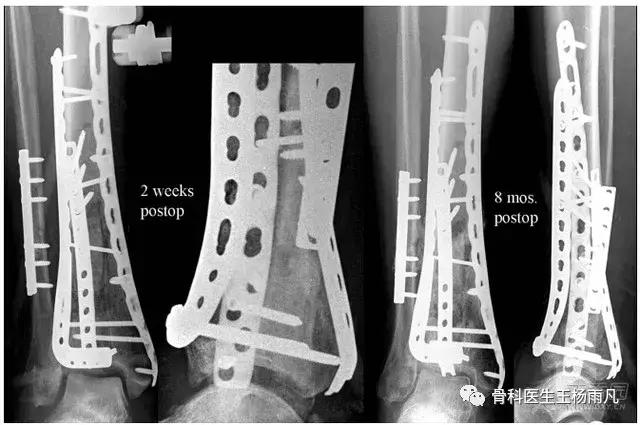

钢板在体内放置时间越长,金属钢板和螺钉之间越容易出现问题,加上周围骨痂骨痂已经牢固包绕钢板生长,再加上十几年前上钢板所用的配套器械早已更新换代,这种钢板取起来特别容易出现滑丝、断钉和取钉困难的情况。除非逼不得已,否则不要取。